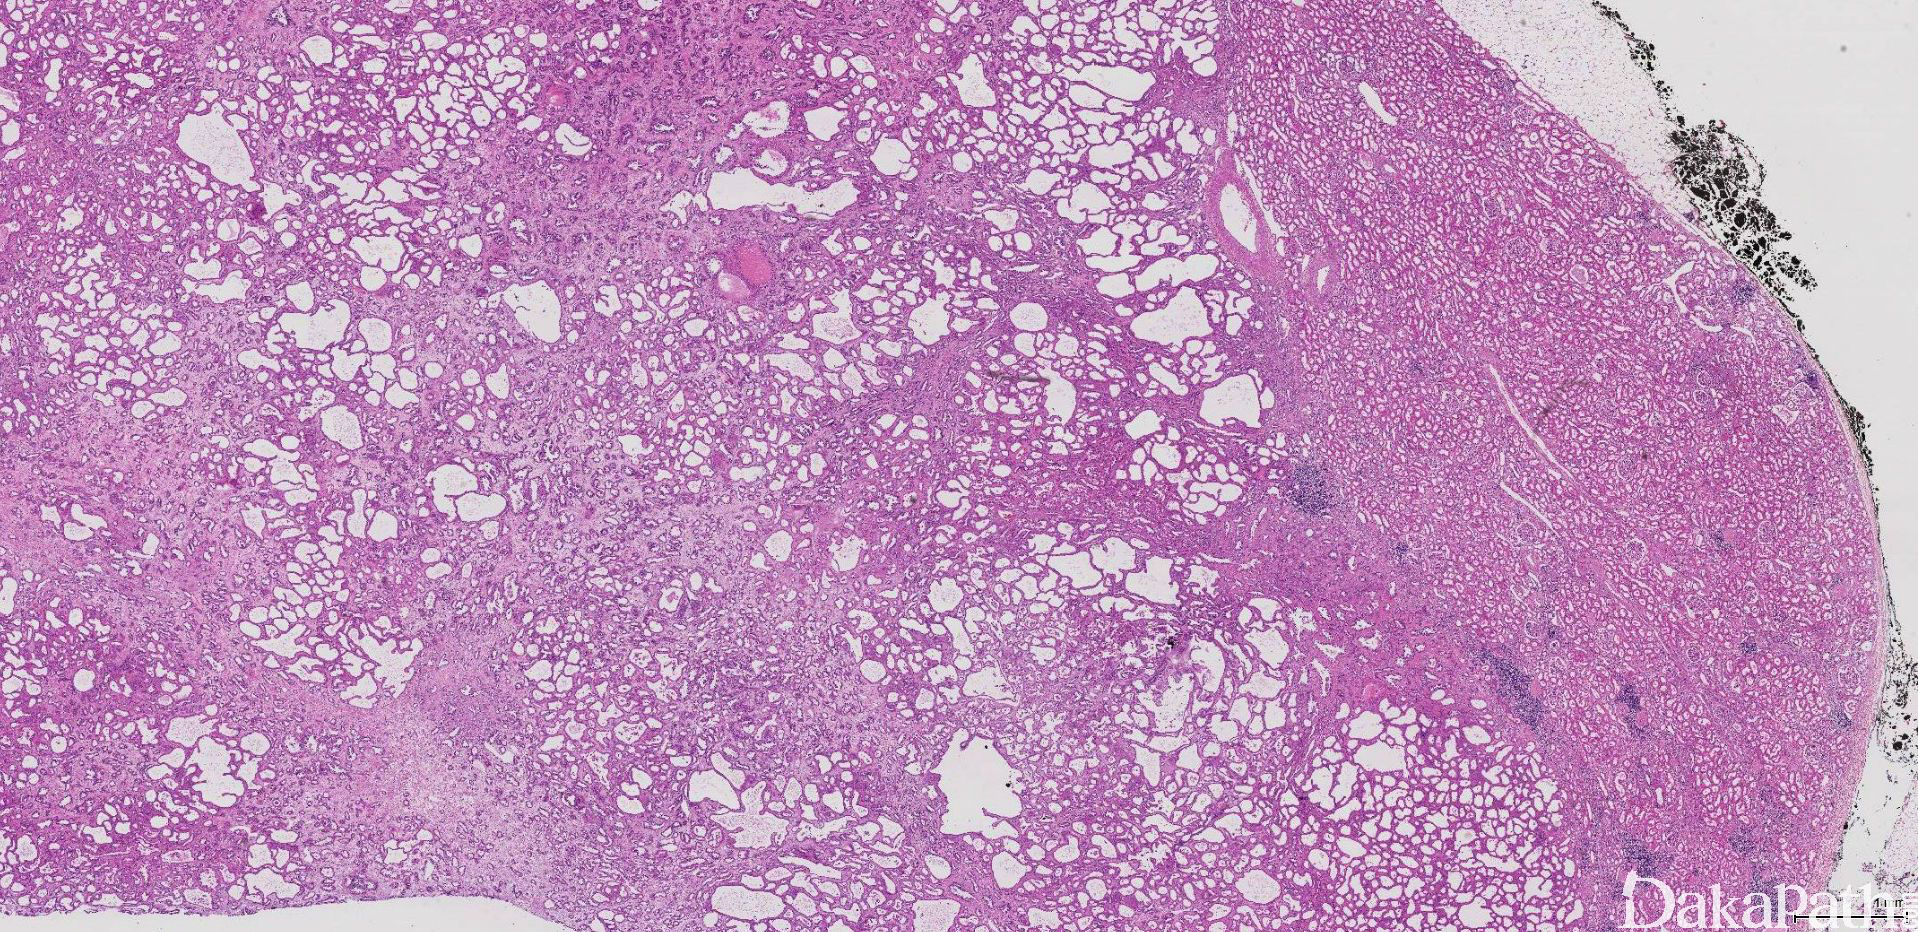

大体检查约 70%的 TCRCC 发生于左肾,通常位于肾皮质或皮髓质交界处,多为单发,肿瘤界限清楚,包膜完整;切面灰白色,呈大小不等的多房囊性,囊壁菲薄,状似“塑胶纸”。瘤体直径 0.7 ~ 17cm(平均约 4.2cm)。

低倍镜下完全由小到中等大的小管和较大的囊肿组成(图 1);被覆瘤细胞单层排列,呈扁平、立方状到柱状、鞋钉样不等(图 2)。管腔或囊腔内容物空,有时可见浅染的嗜酸性分泌物或出血。